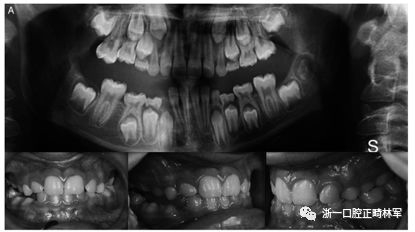

最后,在數(shù)據(jù)庫(kù)中以前沒有報(bào)道的錯(cuò)義變體在外顯子16 c.1765 T>C p.Trp89Arg中發(fā)現(xiàn)。 在同一家庭的三個(gè)成員 - 母親,女兒和兒子(圖3A,B)中發(fā)現(xiàn)的錯(cuò)義變體-負(fù)責(zé)用精氨酸p:Trp89Arg取代氨基酸色氨酸,這是一種具有不同化學(xué)特性的氨基酸。該突變發(fā)生在PTH1R蛋白質(zhì)的胞質(zhì)結(jié)構(gòu)域中,并參與受體與激活細(xì)胞內(nèi)級(jí)聯(lián)信號(hào)的G蛋白的相互作用。此外,計(jì)算機(jī)結(jié)果表明,PTH1R蛋白質(zhì)中的這種氨基酸取代改變了蛋白質(zhì)的結(jié)構(gòu)和功能,因?yàn)樗l(fā)生在蛋白質(zhì)的催化結(jié)構(gòu)域內(nèi)。

圖3.(A,B)兩兄弟的口內(nèi)照片。全景:外顯子16中的家族錯(cuò)義變體c.1765 T>C p.589 W>R

屬于2號(hào)家庭的小女兒(2:2)表現(xiàn)出更復(fù)雜的臨床表現(xiàn),缺乏永久性以及暫時(shí)性系列和囊性結(jié)構(gòu)元素的萌出(圖3A,B)。在哥哥(II:1;圖3A,B)中發(fā)現(xiàn)由于包括多顆恒牙的嚴(yán)重的雙側(cè)后牙開合。最后,患者II:1和II:2的母親表現(xiàn)出雙側(cè)上頜第一磨牙和下磨牙的包埋。發(fā)現(xiàn)前磨牙層面沒有咬合接觸(圖3A,B)。

本研究中確定的低咬合的臨床特征與PFE基于基因診斷和萌出障礙診斷標(biāo)準(zhǔn)的應(yīng)用相一致。對(duì)特定相關(guān)牙科特征的仔細(xì)臨床檢查包括以下內(nèi)容:至少一顆牙包括低咬合,局限于后部區(qū)域,單側(cè)(38%;圖1A)和雙側(cè)呈現(xiàn)(35%;圖1B和2),至少有一個(gè)暫時(shí)性后牙(48%暫時(shí);圖1A,B和3A; 55%永久性,圖3B)。此外,觀察到牙面特征如下:由于受影響側(cè)的側(cè)向開放咬傷的嚴(yán)重程度而引起的垂直骨骼不對(duì)稱(35%;圖1A,B和圖3A,B);由下頜骨側(cè)向偏離組成的面部不對(duì)稱(圖1A,B和圖2;表4)。這種不對(duì)稱在單側(cè)開合患者中更為明顯。進(jìn)一步發(fā)現(xiàn)受影響的患者與先前報(bào)道的患者存在上頜骨收縮和III類牙齒/骨骼關(guān)系(28%;圖1A,B和圖2)。至少有一例患者出現(xiàn)了相對(duì)于9名患者的低咬合。表4總結(jié)了PTH1R的表型結(jié)果和相關(guān)的突變分析(N = 8)。